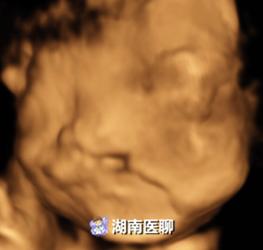

唇腭裂胎儿

正常胎儿